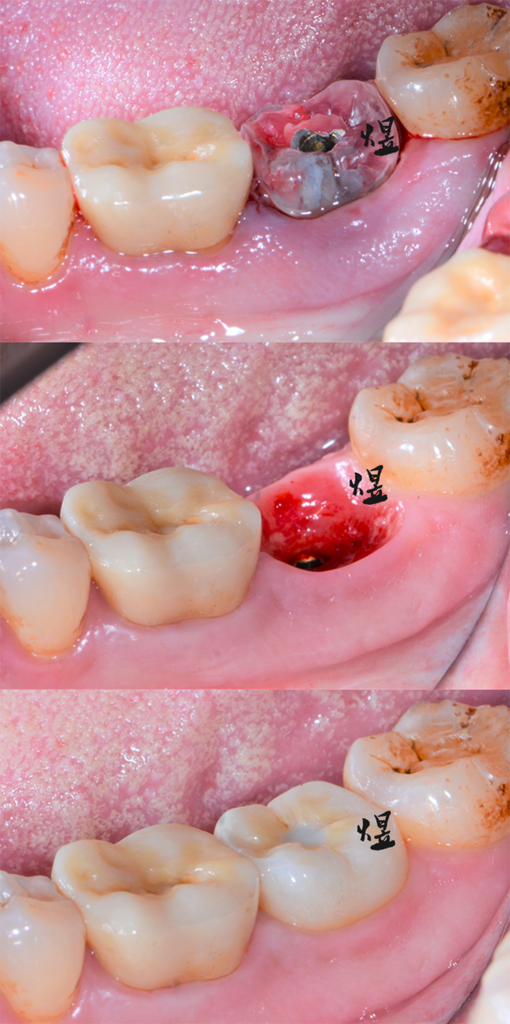

病患牙齒斷裂,同一天完成即拔牙以及人工植牙。

以未來假牙的位置,規劃手術導引板(水晶牙齒),路徑精準安全。

水晶牙齒保留與維持最大量拔牙前軟硬組織的結構與型態;縮短手術時間,微創舒適、更減少製作臨時假牙的時間,不用在診間過度久候。